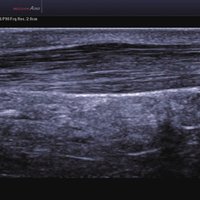

Das Samsung Accuvix A30 ist ein hochwertiges Ultraschallsystem, das mit seiner 3D-Technologie herausragende Ergebnisse ermöglicht. Das Sonographiegerät besitzt 5 Sondenanschlüsse und ist mit 20 unterschiedlichen Schallköpfen kompatibel. Mit dem A30 können Schallköpfe vom Typ Konvex, Mikrokonvex, 3D-Konvex, CW, Phased Array, Linear und Endokavitär verwendet werden. Bei zwei der Sonden handelt es sich um S-VUE Ultraschallsonden, die durch ihre höhere Bandbreite noch feinere Scans erzeugen.

Das Samsung Accuvix A30 ist mit 20 unterschiedlichen Schallköpfen kompatibel. Folgende Konvex-, Mikrokonvex-, 3D-Konvex-, CW-, Phased Array-, Linear- und Endokavitär-Schallköpfe werden unterstützt:

2 L5-13IS Linear 6-12 MSK, Weichteile, Gefäße, Brust

3 L5-13/50mm Linear 5-13 MSK, Weichteile, Gefäße

4 LS6-15 Linear 6-15 MSK, Weichteile, Gefäße

5 L7-16IS Linear 7-16 MSK, Weichteile, Gefäße, weibliche Brust, Pädiatrie, Oberfläche